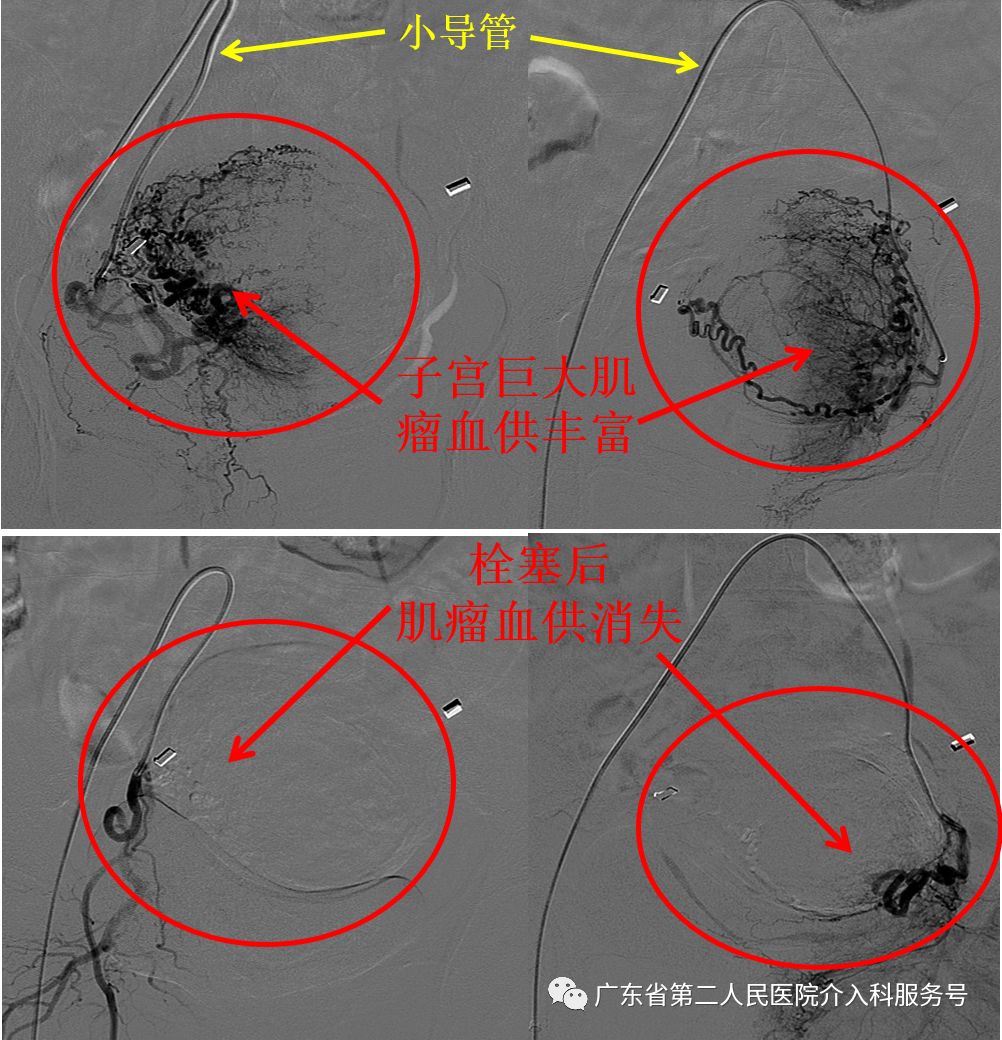

梁女士的月经量越来越多伴有大量血块,淋沥不净及严重的贫血是由于子宫巨大肌瘤导致。梁女士住院完善相关检查,适合做子宫动脉栓塞治疗(针眼妙方……大腿根部只有2毫米(约米粒大小)的微创针眼),则在广东省第二人民医院介入科给予梁女士局部麻醉下行子宫动脉超选择栓塞治疗子宫肌瘤。子宫动脉超选择栓塞治疗是经右大腿根部的股动脉在机器的监视下送入小小导管找到子宫肌瘤的供血动脉,然后将子宫肌瘤的供血动脉栓塞,最后拔除导管结束治疗。

下图为梁女士的子宫肌瘤血供丰富(肌瘤血液供应充足,生长旺盛),微创栓塞治疗后子宫肌瘤血供消失(肌瘤缺乏生长的血液后则坏死、吸收、缩小)。